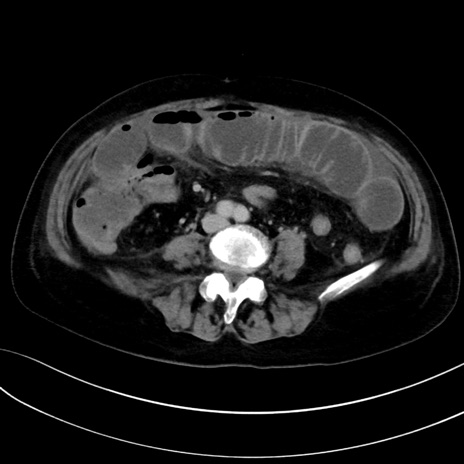

症例13 CT(横断像)1日半後